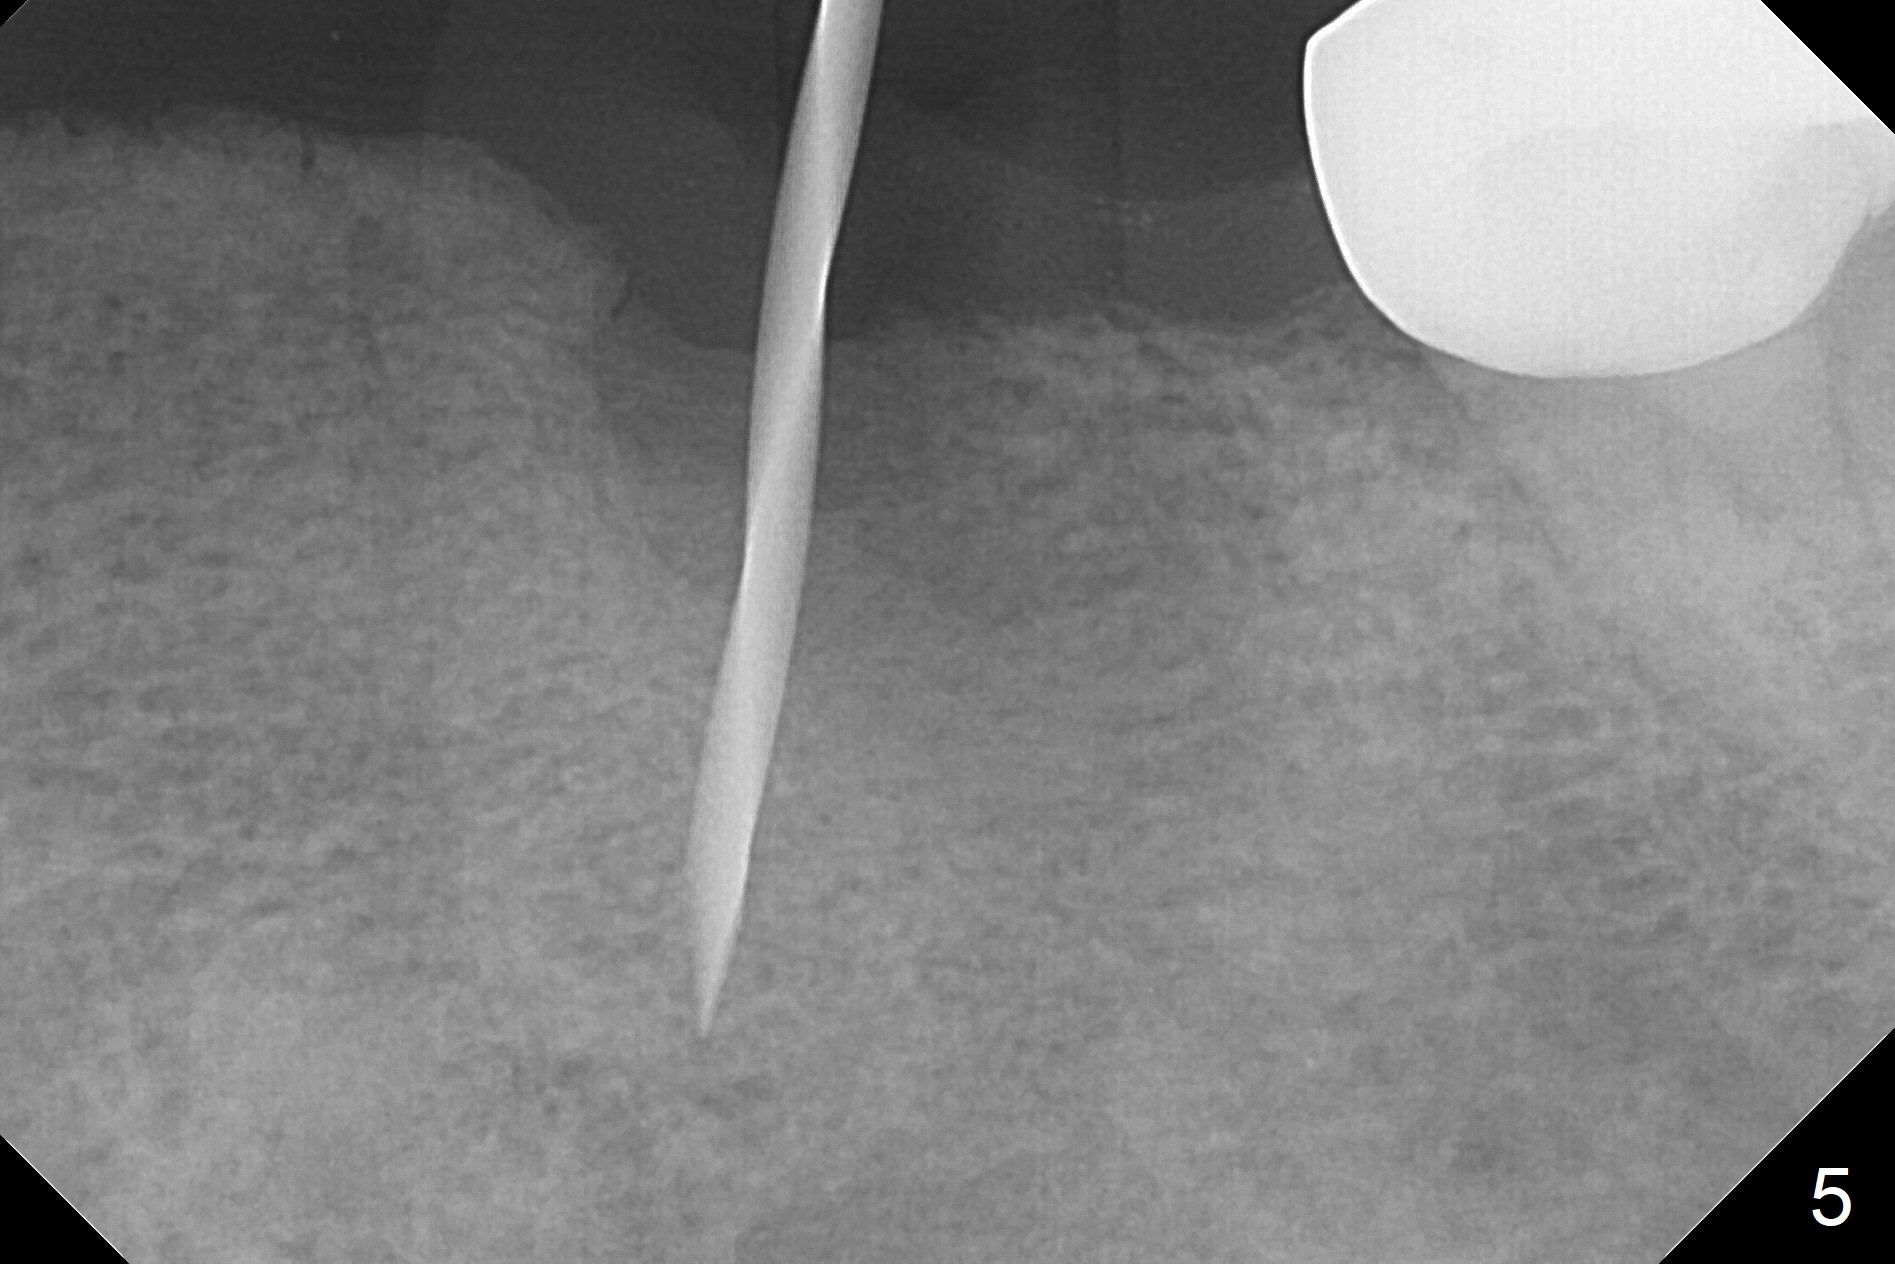

After removal of the pontic at #19 and retainer at #20 (Fig.1) and of vertically fractured root, the buccal plate is found to be defective (Fig.2 *). An implant will be placed as lingual as possible. Since the apex of the affected tooth is coronal to the Mental Loop (Fig.3 red dashed line), an osteotomy (Fig.4 yellow arrow) to be established in the mesial slope (blue dashed line) after extraction (black area) appears to be safer than that along the long axis of the tooth. The initial osteotomy is accomplished by free hand (Fig.5), but when the lower RPD is inserted, the superior end of the 1.5 mm pilot drill is distal (Fig.6). When the trajectory is corrected using the RPD as a surgical guide at the same depth (17 mm gingival level), brisk hemorrhage is from the osteotomy without severe pain. After hemostasis is achieved by packing the socket with Osteogen plug and bone graft and packing bone graft into the osteotomy, 3.3 mm Magic Drill is used for 14 mm. A 4x11 mm IBS implant is placed with 60 Ncm (Fig.7). The implant is then placed deeper, followed by placement of a 4.5x4(3) mm abutment and further bone graft (Fig.8). Finally the implant/abutment complex is apparently in an acceptable mesiodistal position with a large buccal gap which has been filled by bone graft (Fig.9 *). In fact the Mental Loop seems to have been not violated in the procedure (Fig.10). X-ray is taken 3 and 6 months postop. Bone graft (Fig.11,12 (CBCT) *) appears to remain over the buccal (B) surface of the implant coronally 13 months postop (7 months post cementation). The gingiva at #19 and 20 is apparently healthy 8 months post cementation except mild recession at #20 (Fig.13).